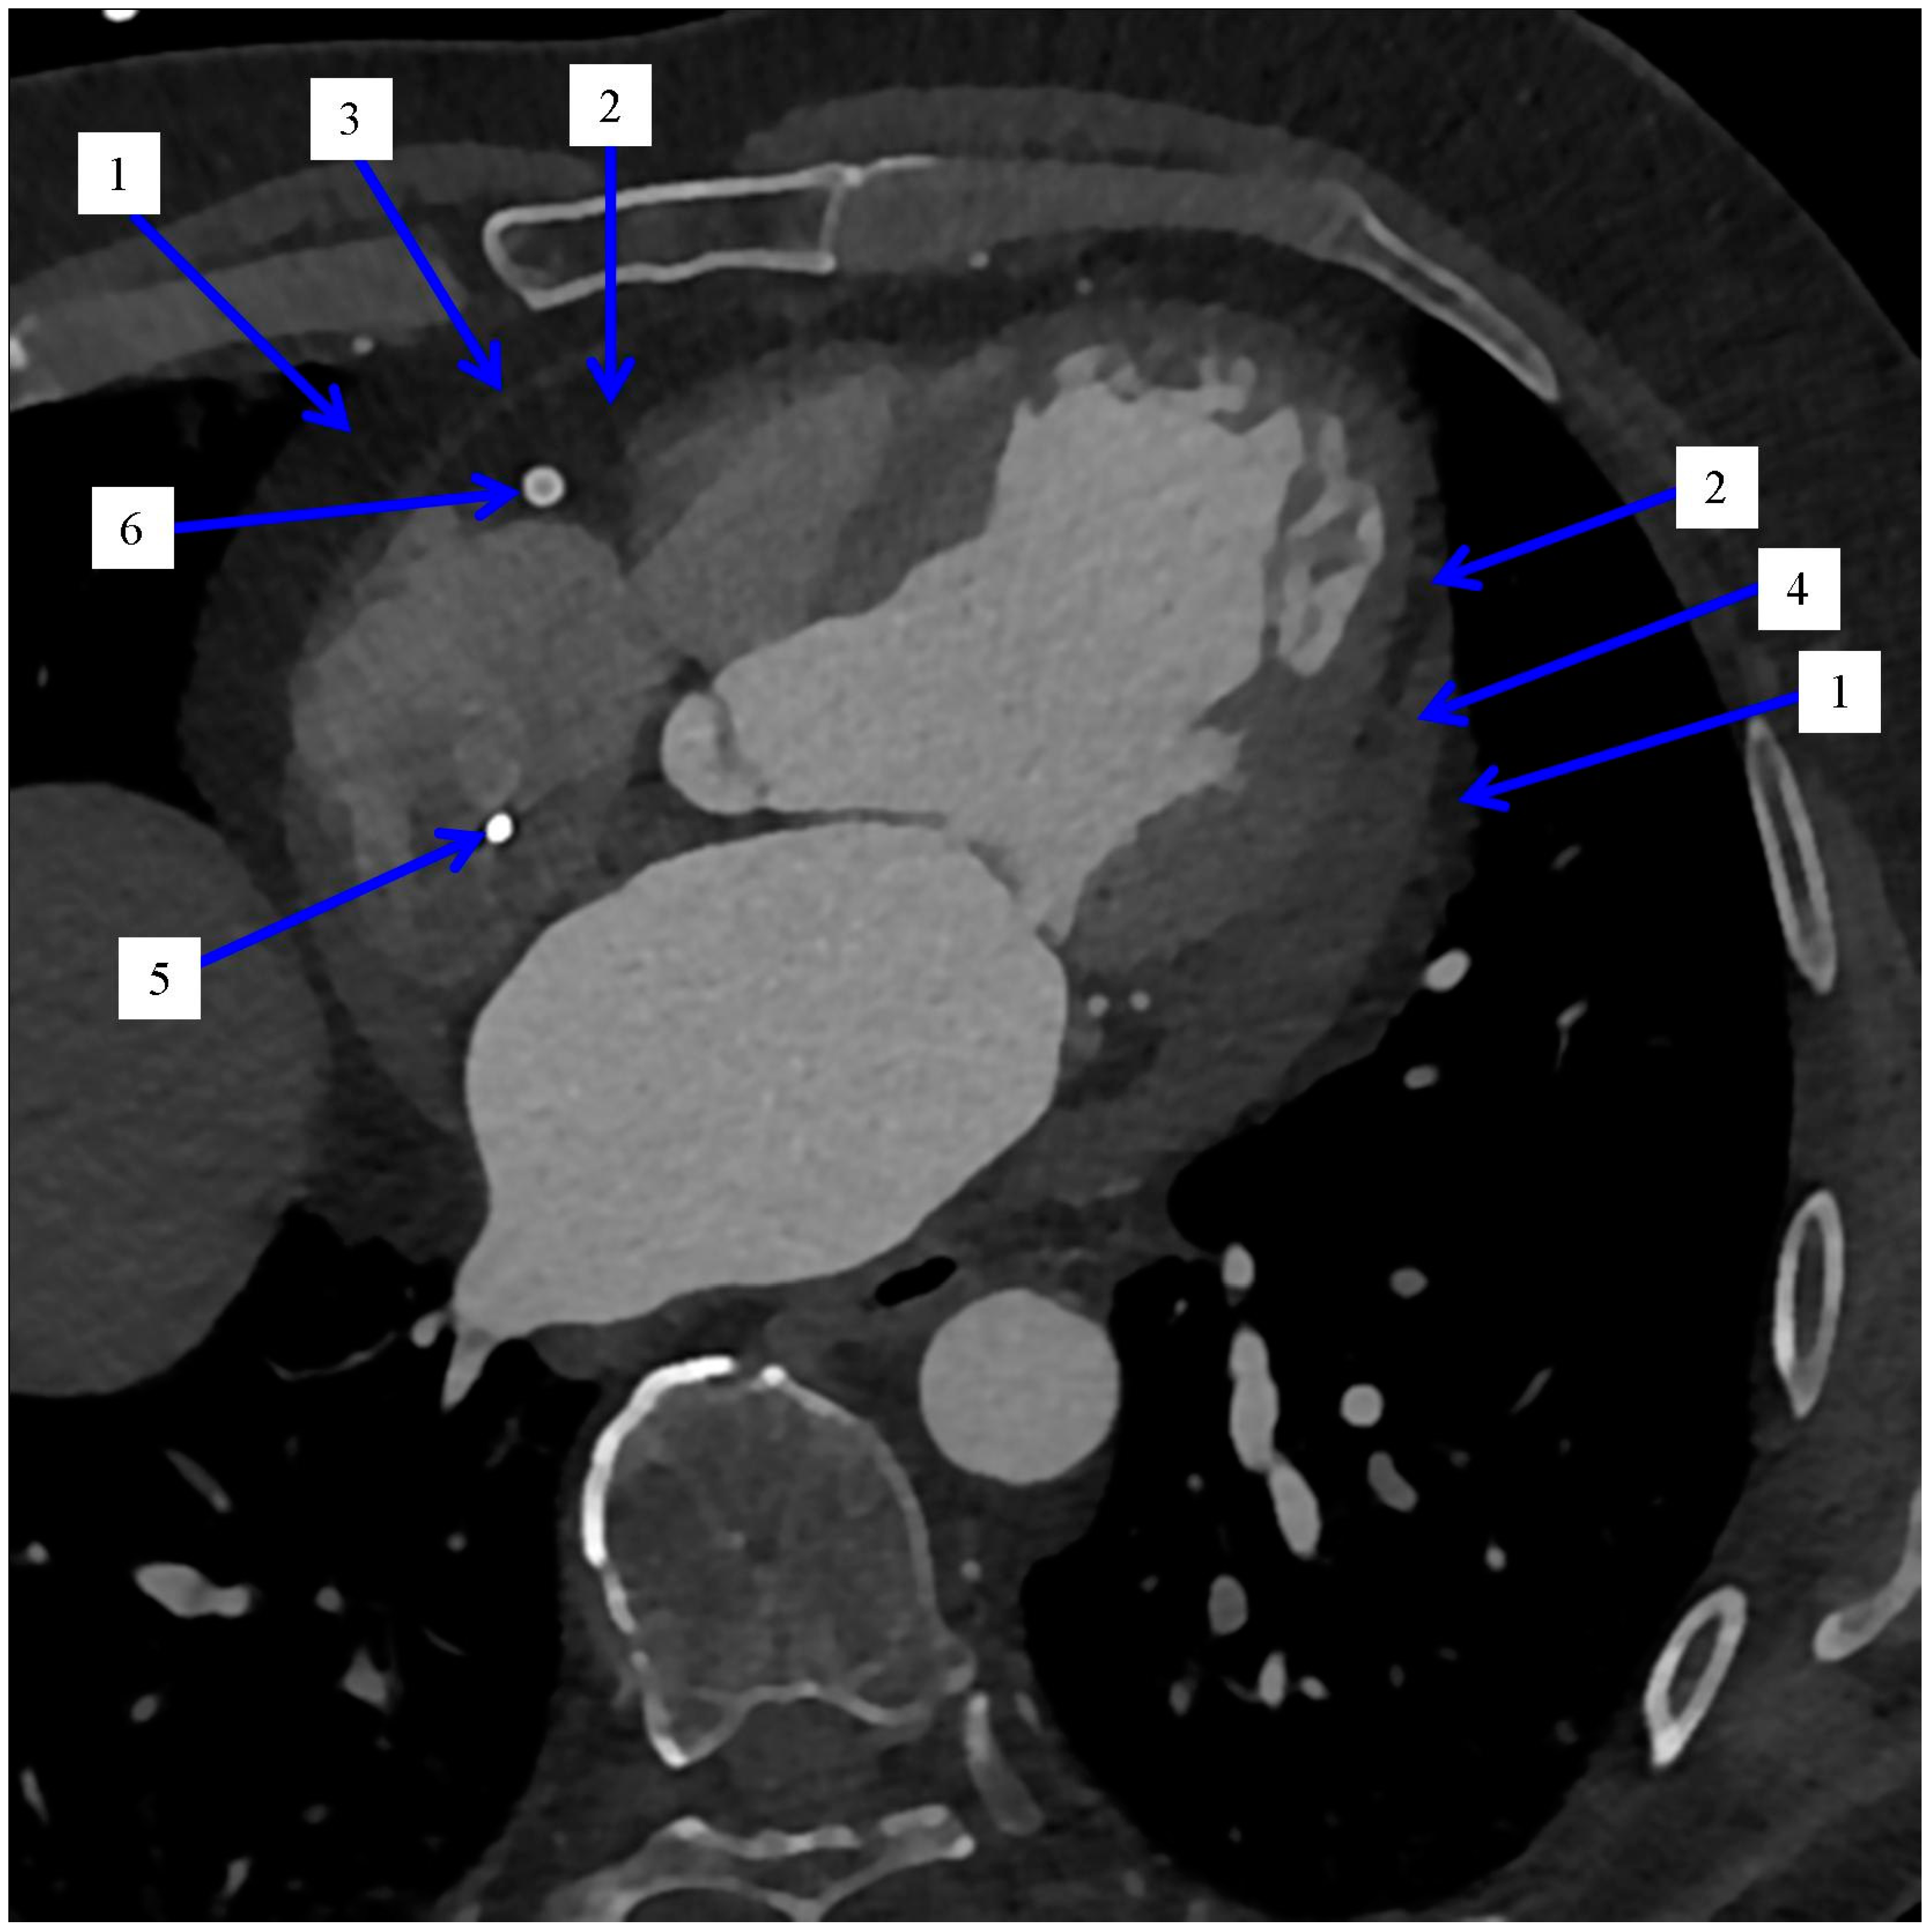

2.1. Distribution of the Epicardial Adipose Tissue

2.2. Imaging and Measurement Methods of Epicardial Adipose Tissue